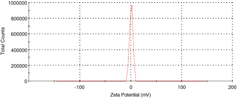

Hesperetin loaded nanoparticles were prepared from Eudragit® E copolymer using nanoprecipitation method. The functional performance of nanoparticles based delivery systems depends on the physicochemical properties of the nanoparticles, such as size, morphology and physical state. Dynamic light scattering analysis revealed that the formulated nanoparticles had an average size of 180 nm (figure 1) with slight positive potential (+ 0.962 mV) (figure 2).

Standard image High-resolution imageFigure 2. Zeta potential distribution of HETNPs.

In the present study, hesperetin-loaded nanoparticles were prepared by nanoprecipitation method and its anticancer efficiency in KB oral cancer cells was tested. Particle size of nanoparticles plays a crucial role in their antitumor activity and in vivo distribution [32, 33]. Smaller nanoparticles show a higher accumulation at tumor sites and prolong in vivo half-life due to their avoidable capture by the reticuloendothelial system [34, 35]. From the results of DLS technique, the average particle size is nearly 180 nm. TEM results clearly indicated that particles have nearly spherical shape with an average size of ∼55 nm. The size measured by DLS is that of water-swollen particles (hydrodynamic diameter), whereas the size deduced from TEM measurement corresponds to particles in a dried state. Therefore, the particle size from TEM measurements in a dried state cannot be compared with the values from DLS measurements and DLS gave higher values compared to TEM [36]. Particle size is controlled around 180 nm which is in favor of the antitumor activity and prolongs efficacy of HETNPs. Nanoparticles with small particle size (< 200 nm) are reported to have cross vasculature endothelia and accumulated at tumor sites via the enhanced permeation retention (EPR) effect [23]. It was further established that the optimal particles size is ranging from 20 to 400 nm [37]. Hesperetin-loaded nanoparticles are thus convenient to benefit from the EPR effect. Further, the zeta potential values are close to zero. The factor which might be responsible for such an effect can be the presence of residual PVA on the nanoparticles surface.